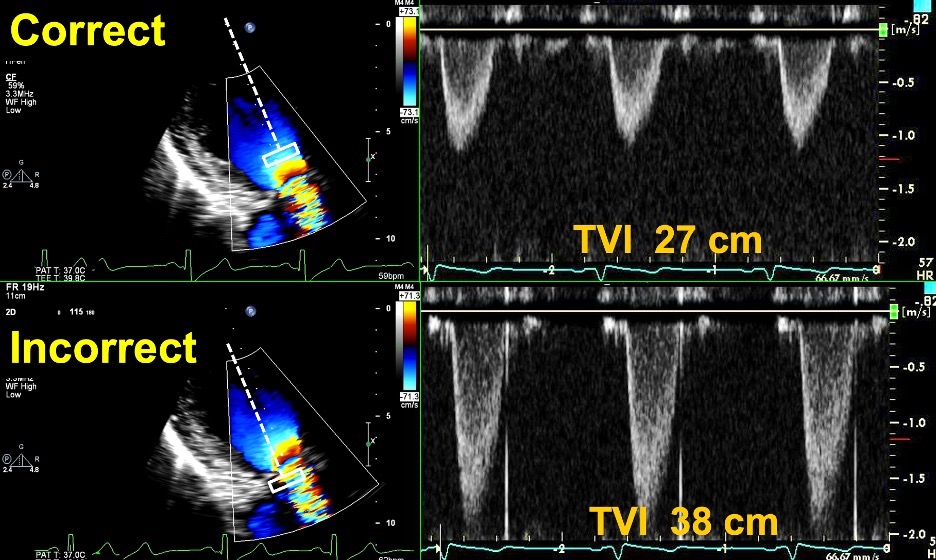

Fig. 7.Echocardiographic imaging of a patient with a mitral bioprosthesis and heart failure symptoms found to have prosthetic thrombosis.

Top Left: Continuous Wave Doppler in a patient with a

31 mm Hancock porcine mitral bioprosthesis who presented with dyspnea on exertion

and lightheadedness. The mean gradient was 12 mmHg with a heart rate of 51 and a

pressure halftime of 280 msec. The DVI was 5.7, with an EOAi of 0.44

cm